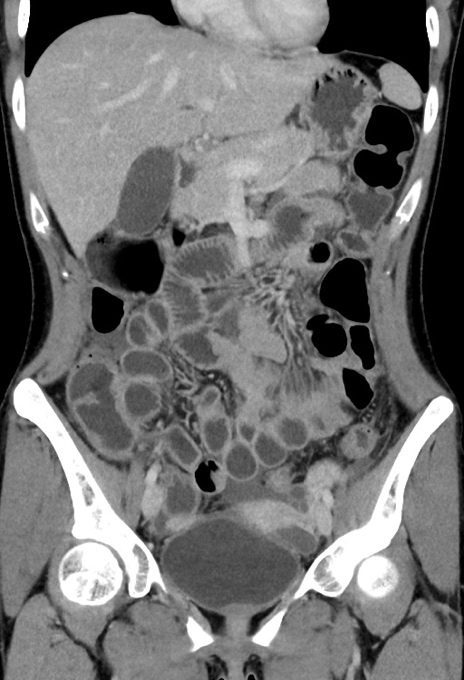

症例17(冠状断像)

【症例】20歳代女性

【主訴】嘔吐、下腹部痛

【現病歴】昨日夕食後に嘔吐し下腹部痛が出現。本日になっても嘔吐持続し改善しないため来院。

【身体所見】意識清明、BT 37.2℃、BP 108/67mmHg、腹部:平坦、やや硬、下腹部正中から右にかけて圧痛あり、反跳痛軽度あり、tapping pain(+)。

【データ】WBC 13600、CRP 14.94